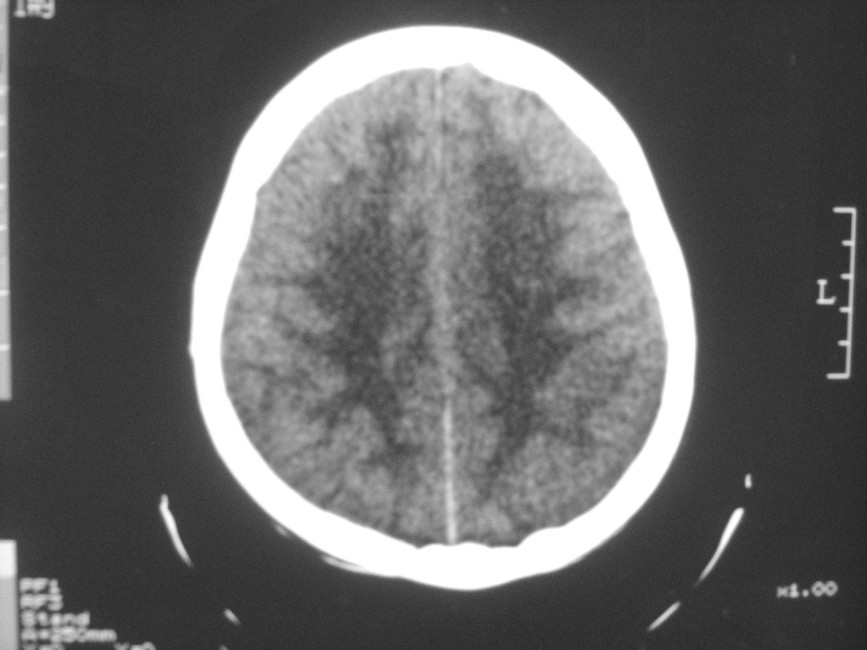

以下是引用zzyy在2008-6-16 10:13:00的发言:[br]两侧脑白质呈对称性密度减低,病儿有发热及脑膜刺激征。考虑急性病毒性脑炎。